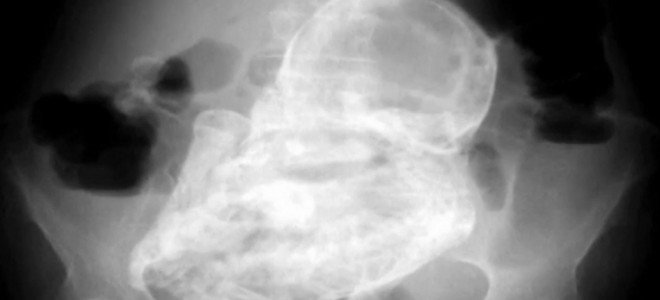

Μια 80χρονη γυναίκα «κυοφορούσε» για 40 χρόνια ένα έμβρυο χωρίς να το γνωρίζει. Στο νοσοκομείο της Μπογκοτά οι γιατροί δεν πίστευαν στα μάτια τους όταν αποδείχτηκε ότι η αιτία για τις γαστρεντερικές διαταραχές της ηλικιωμένης γυναίκας ήταν ένα έμβρυο.

«Οι αρχικές εξετάσεις έδειξαν κάτι ασυνήθιστο, που αρχικά πιστέψαμε ότι ήταν όγκος. Αποδείχθηκε, όμως, πως ήταν ένα έμβρυο», δήλωσε μια από τους γιατρούς που παρακολουθούν τη γυναίκα. Λόγω κάποιας επιπλοκής το έμβρυο μετακινήθηκε στην κοιλιακή χώρα, όπου και παρέμεινε ως «απολίθωμα» χωρίς να δημιουργήσει προβλήματα υγείας όλα αυτά τα χρόνια.